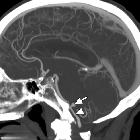

Bilateral

medial medullary infarction in association with a vertebral artery aneurysm. Sagittal MIP reconstruction of CT angiogram shows aneurysm (arrow) connected to right vertebral artery (arrowhead) by a narrow aneurysmal neck.